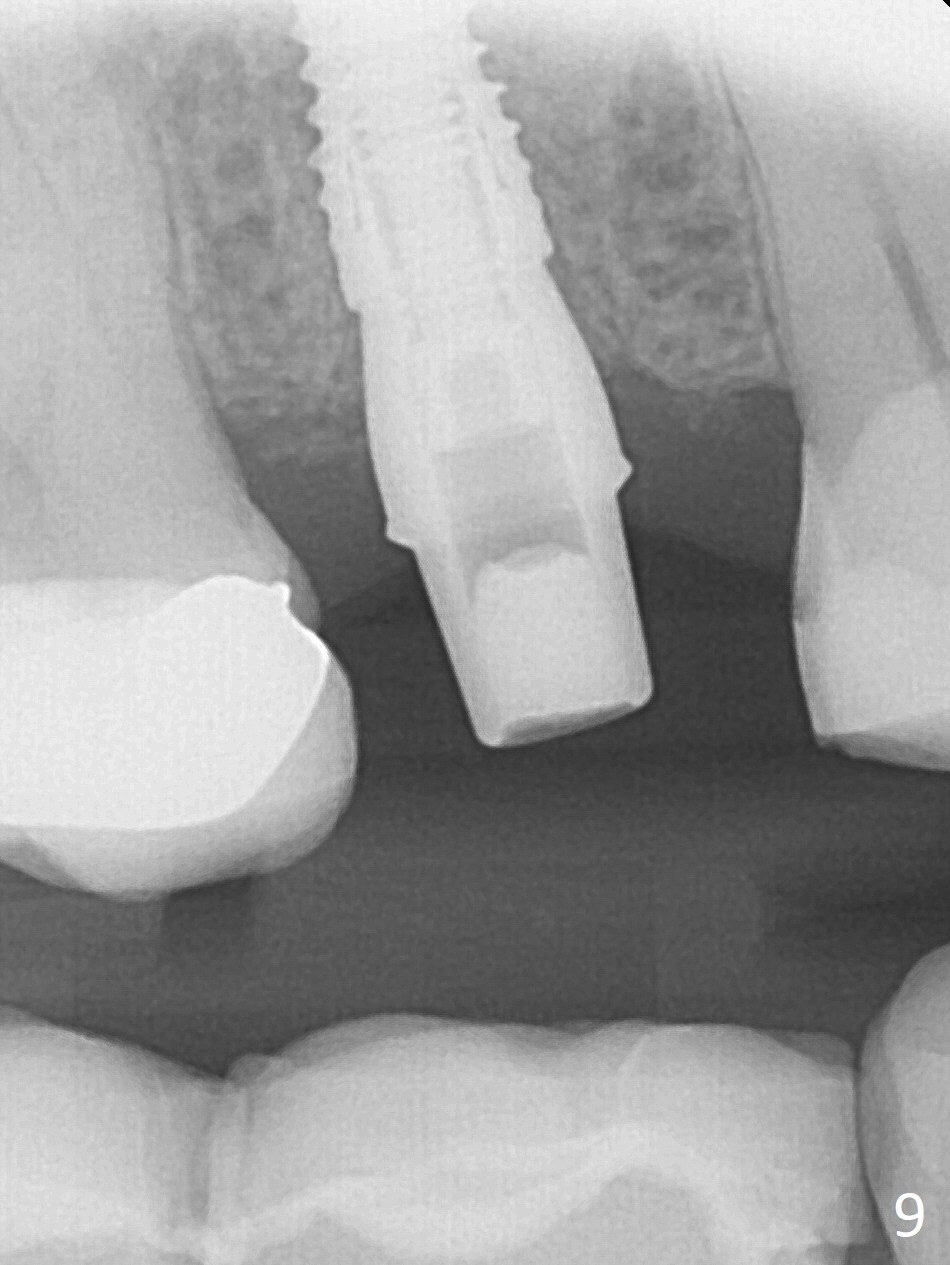

After extraction of the tooth #4 with palatally subgingival fracture (Fig.1 ^), white hard tissue is found in the socket, the density of which is hard (Fig.2 D). When osteotomy passes this portion of the bone (Fig.3 red dashed line), bone density feels reduced suddenly. The osteotomy is moved mesially slightly (Fig.4 (2.7 mm drill)). When a 3.8x15 mm dummy implant is placed with stability, there is an apical space (Fig.5 red dashed line). Therefore the final implant is longer (3.8x18 mm, <30 Ncm, Fig.6, 7). Vanilla graft is placed around the implant and a 4.5x4(4) mm abutment is placed immediately for an immediate provisional (Fig.8). Although the provisional easily dislodges in spite of remake, the implant seems osteointegrated with decreased space 4 months postop (Fig.9). The gingiva is healthy, although it covers the abutment margin partially. Gingivectomy appears necessary for impression.